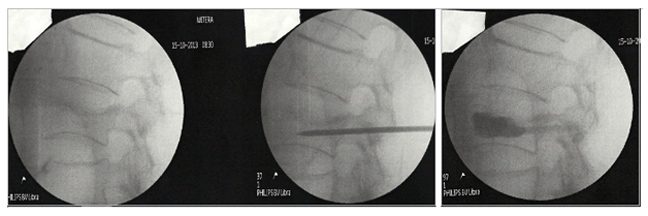

Σε περιπτώσεις με βαρεία πάθηση των πνευμόνων ή της καρδιάς, συνιστάται η λήψη αναλγητικών για διάστημα τριών μηνών, οπότε το κάταγμα έχει κολλήσει. Σε όλους τους άλλους η θεραπεία είναι η έγχυση ακρυλικού τσιμέντου (κυφοπλαστική) που σταθεροποιεί τον σπόνδυλο και περνάει ο πόνος αμέσως.